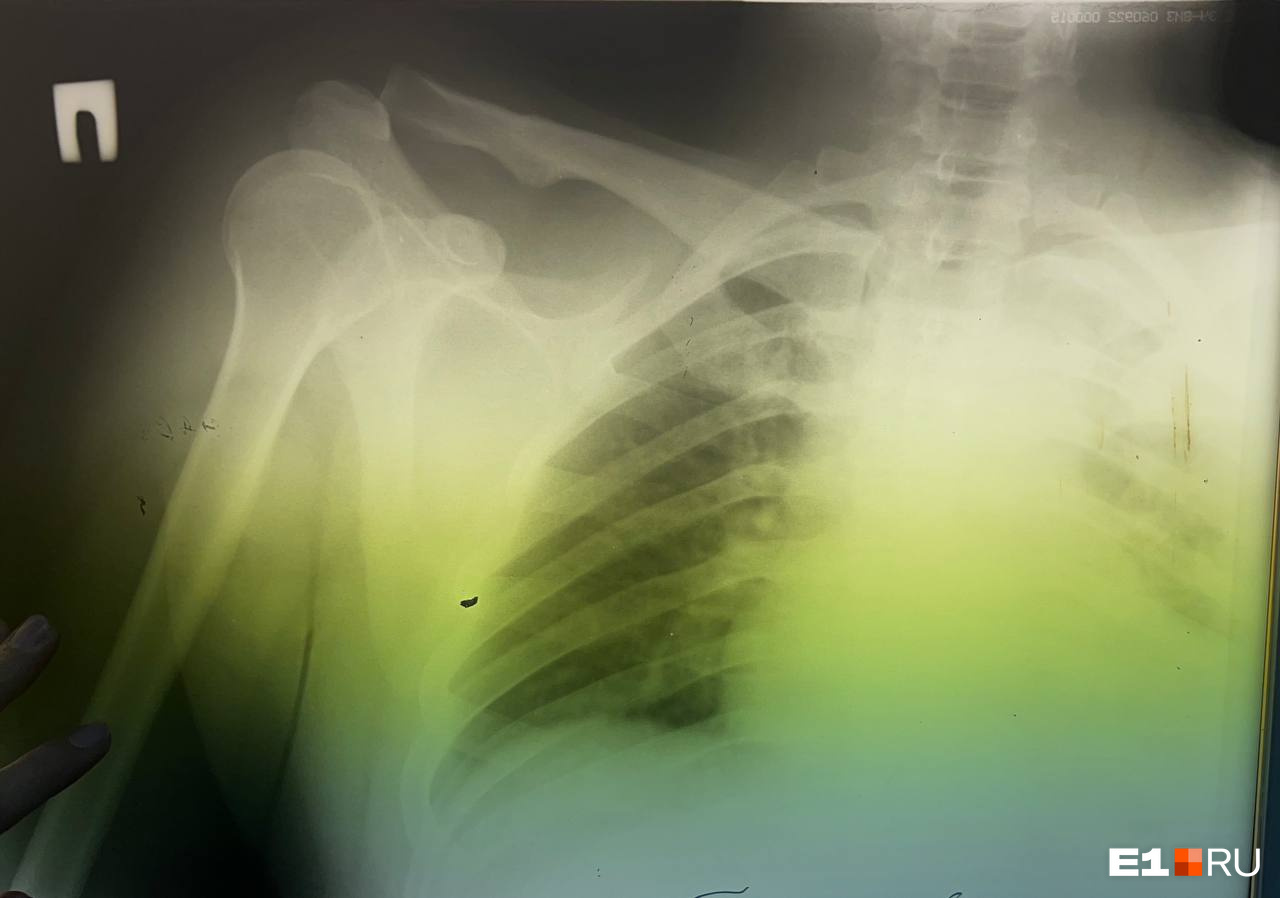

Супруги из Екатеринбурга приехали отдохнуть на горнолыжный комплекс «Пильная парк» (находится недалеко от Первоуральска), но получили серьезные травмы из-за лихача, нарушившего правила ГЛК. Все произошло 13 января. У пострадавшего мужчины разрыв правого акромиального-ключичного сочленения (АКС) и вывих правой ключицы.

Акромиально-ключичное сочленение (АКС) — это связующая точка верхней конечности с остальным скелетом. Иначе говоря, кость скрепляется со скелетом именно благодаря этой связке.